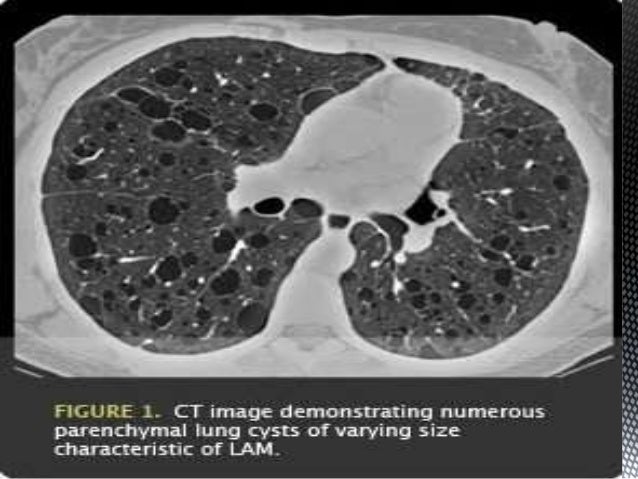

Лам легких

Лам легких 113 фото